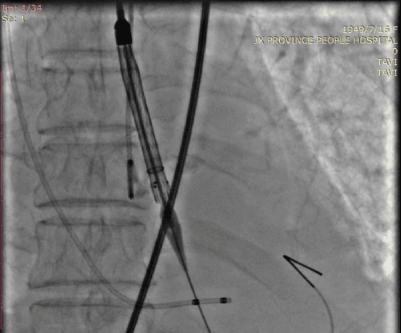

主动脉根部造影未见明显反流,瓣叶活动受限,开口面积小,猪尾导管因无冠窦钙化未放到窦底。

采用22mm球囊预扩有一点腰征,左右冠均显影。

稍高位释放

稍高位释放,释放过程中略微下移。

瓣膜展开后可见接近标准位,且无瓣周漏。

5月19日,朱奶奶被送入介入室行经导管主动脉瓣置换术,由于下肢血管入路极度扭曲,并且低血压,难以耐受长时间麻醉及手术,洪浪院长团队简化方式建立入路,再进行全麻,并迅速完成垮瓣、球囊扩张及Venus A 26mm瓣膜释放,术后造影提示瓣膜位置良好,无瓣周漏,左心室与主动脉压差从术前139mmHg降至7mmHg,手术非常成功。从病人上台至股动脉缝合共耗时100分钟,术后转入CCU进行复苏,继续监测生命体征。